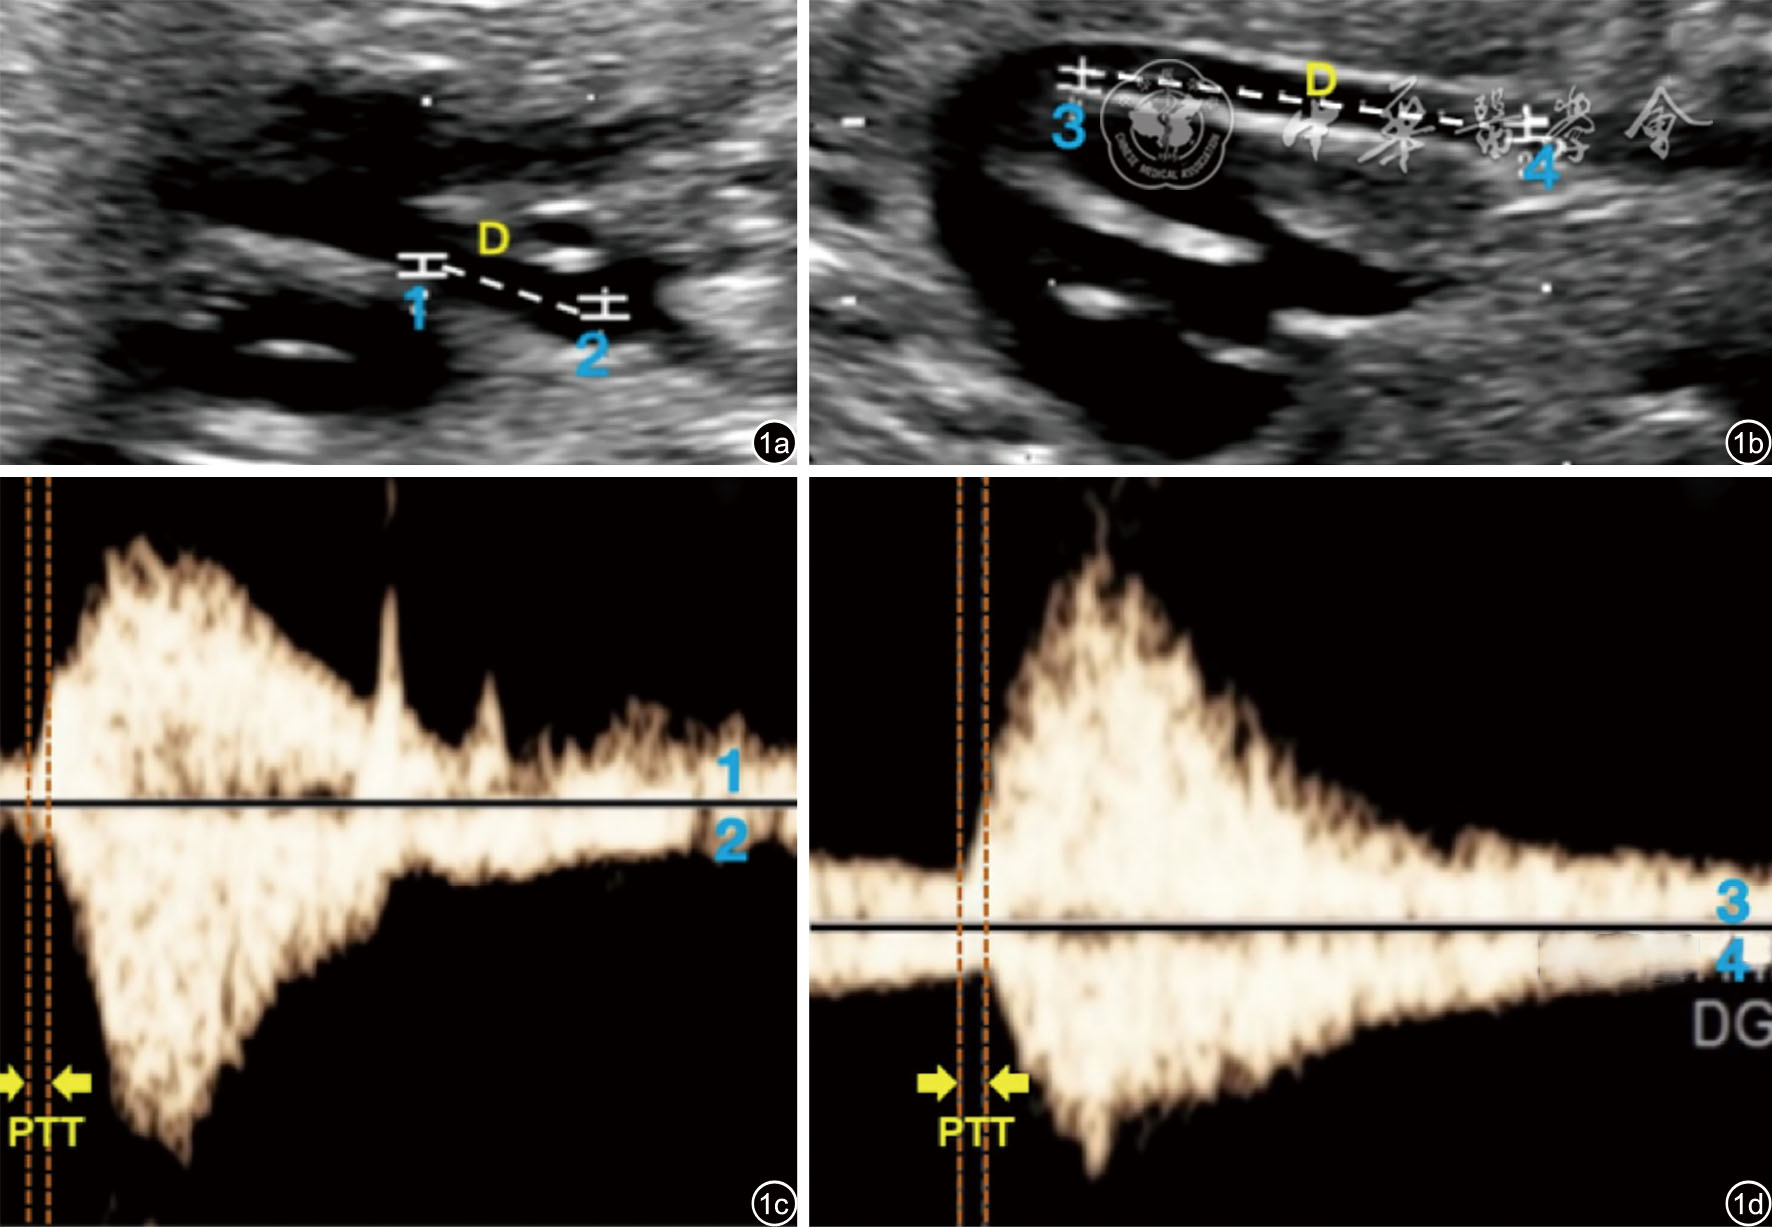

图1 胎儿主动脉脉搏波传导速度(PWV)分析。图a为胎儿升主动脉长轴切面二维图像(D表示升主动脉上近心点1与远心点2之间距离);图c为点1与点2分别对应的脉搏波频谱1、2(PTT表示同一心动周期内脉搏波由点1传播至点2的时间差);图b为胎儿降主动脉长轴切面二维图像(D表示降主动脉上近心点3与远心点4之间距离);图d为点3与点4分别对应的脉搏波频谱3、4(PTT表示同一心动周期内脉搏波由点3传播至点4的时间差);PWV=D/PTT